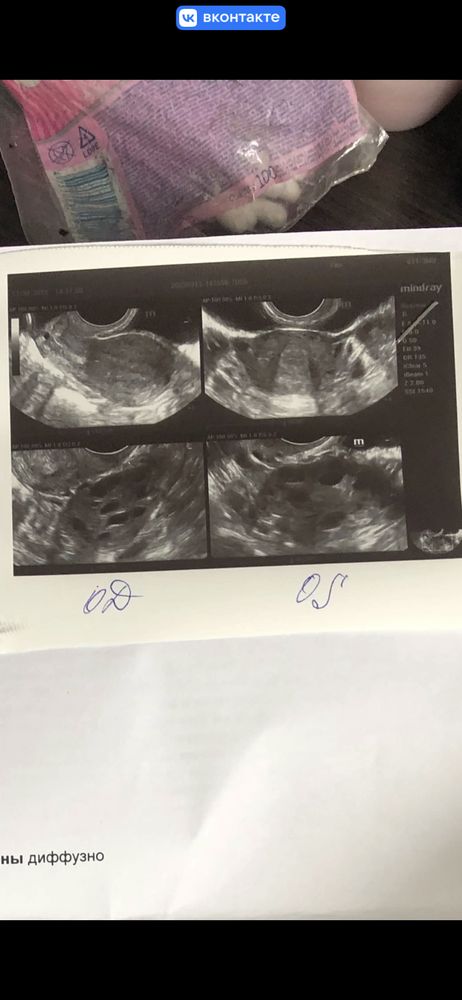

Поставили диагноз мультифолликулярные фолликулы

Эва → Зачатие Гинекологические заболевания планирую беременность Екатеринбург Мфя или спкя? Поставили диагноз мультифолликулярные фолликулы Посмотрите еще 20 записей на эту тему Марина Балей Может мультифолликулярные яичники у меня то же самое 0 28.11.2023 Ответить Эва Мама девочки (1 год) Екатеринбург Марина, а с ними можно забеременеть? 0 30.11.2023 Ответить Марина Балей Иван Будько, да но нужно наблюдение врача 0 30.11.2023 Ответить Желтое тело 18 мм норм или мало? на 2 день после овуляции Дюфастон при планировании 1 табл в день или 2 табл? Похожие записи Спкя СПКЯ- диагноз, который можно победить! Диагностика СПКЯ СПКЯ СПКЯ Чаты Беременных Выберите чат: Июлята-2026 Августята-2026 Сентябрята-2026 Октябрята-2026 Ноябрята-2026 Декабрята-2026